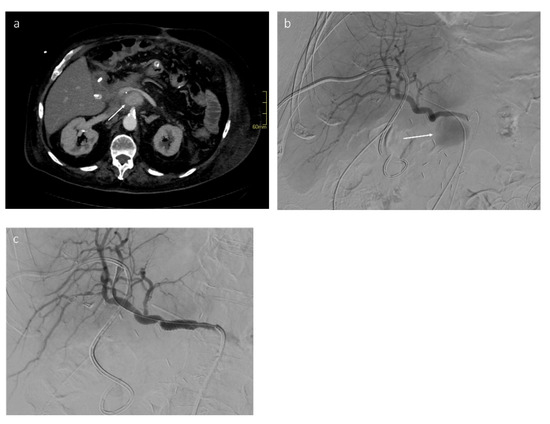

- Biondetti, P.; Fumarola, E.M.; Ierardi, A.M.; Carrafiello, G. Bleeding complications after pancreatic surgery: Interventional radiology management. Gland. Surg. 2019, 8, 150–163. [Google Scholar] [CrossRef] [PubMed]

- Venturini, M.; Marra, P.; Colombo, M.; Alparone, M.; Agostini, G.; Bertoglio, L.; Sallemi, C.; Salvioni, M.; Gusmini, S.; Balzano, G.; et al. Endovascular treatment of visceral artery aneurysms and pseudoaneurysms in 100 patients: Covered stenting vs transcatheter embolization. J. Endovasc. Ther. 2017, 24, 709–717. [Google Scholar] [CrossRef]